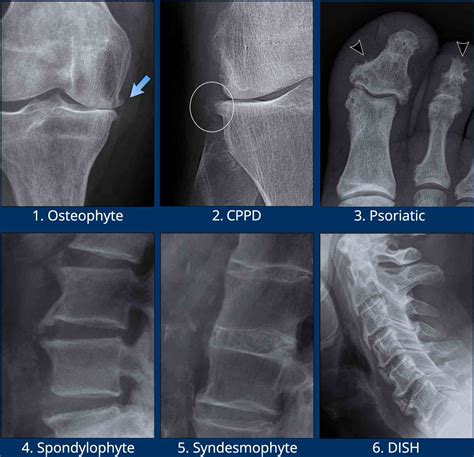

Alright, first up, let’s talk about osteophytes . Basically, these are bone spurs – abnormal growths of bone that form along the edges of bones. Imagine your bones as having a smooth, clean edge. Osteophytes are like little bumps or protrusions that develop on those edges. They’re typically caused by the body’s attempt to repair damage. The body, in its wisdom, sometimes overcompensates, leading to extra bone formation. Think of it like this: if you scrape your knee, your body rushes to heal the wound, and sometimes, the healing process leads to a scar. Osteophytes are kind of like bone scars. Now, they’re super common, especially as we get older, and they can occur in various parts of the body, such as the spine, hips, knees, and feet. They might not always cause problems, but when they do, they can lead to pain, stiffness, and restricted movement. In the spine, for example, osteophytes can press on nerves, causing pain, tingling, or numbness in the arms or legs. In the hips or knees, they can contribute to the development of osteoarthritis, a condition characterized by the breakdown of cartilage and joint pain. The formation of osteophytes is often associated with the natural aging process, as the cartilage that cushions the joints gradually wears away. This wear and tear can trigger the body’s repair mechanisms, leading to the formation of bone spurs. Other factors, such as injury, overuse, and certain medical conditions like osteoarthritis and rheumatoid arthritis, can also increase the risk of osteophyte development. Diagnosing osteophytes typically involves a physical examination and imaging tests, such as X-rays, MRI scans, or CT scans. These imaging techniques can reveal the presence, size, and location of the bone spurs, helping healthcare providers assess their impact on the surrounding tissues and structures. Treatment options for osteophytes vary depending on the severity of symptoms and the location of the spurs. In many cases, conservative treatments such as pain relievers, physical therapy, and lifestyle modifications can effectively manage symptoms. In more severe cases, when osteophytes cause significant pain or impair function, surgical intervention may be considered to remove the bone spurs or address the underlying cause.